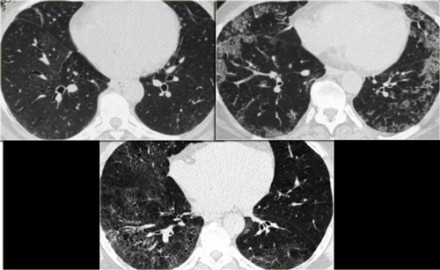

Upper lobe predominant centrilobular ground glass, OR prominent mosaic pattern

Hypersensitivity Pneumonitis

(subacute)

lobular GGO

Need constellation of findings to dx: exposure to an offending antigen, characteristic signs and symptoms, abnormal chest findings on physical examination, and abnormalities on pulmonary function tests and imaging

chronic hypersensitivity pneumonitis

Mosaic pattern with areas of ground-glass atenuation and areas of low attenuation.

Fibrosis and parenchymal distortion in a mid zone distribution.

left vs right?

Left UIP w honeycombing

Right Chronic HP